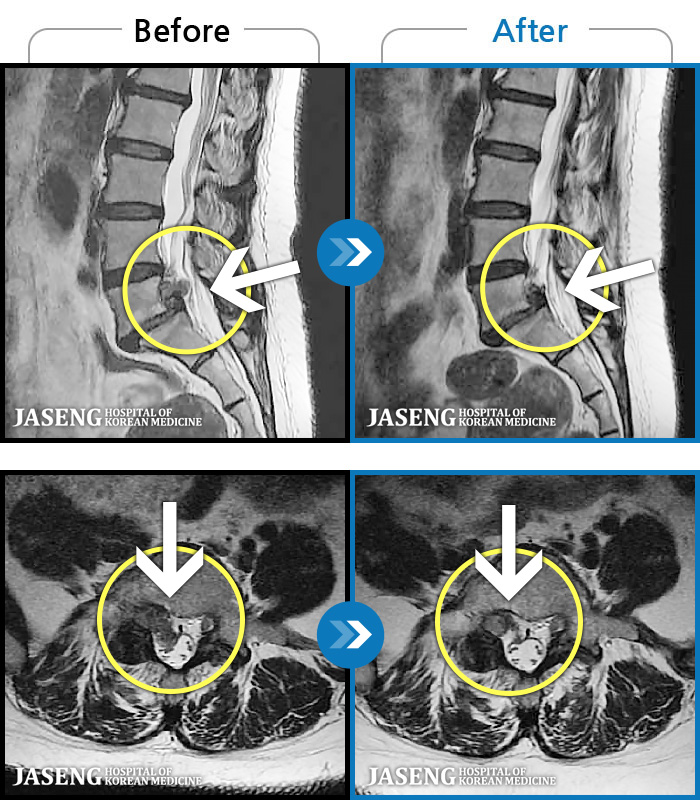

[뱸] 19.11.28~25.05.06